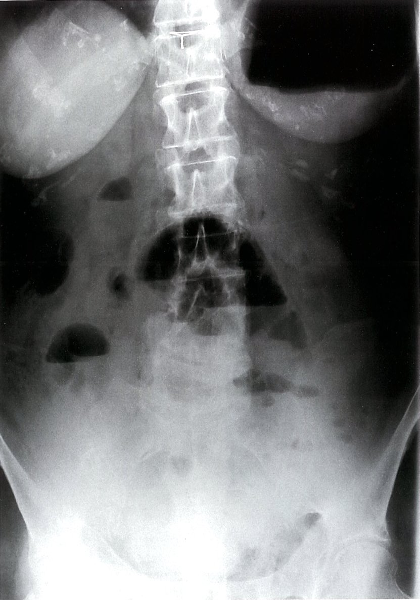

Radiological appearances:

Dilatation of bowel loops proximal to the obstruction: 3-6-9 rule :To help guide the identification of bowel dilatation on imaging. Transverse diameter greater than the following indicates dilation: Small bowel > 3 cm Large bowel > 6 cm Cecum > 9 cm

- SBO: Dilated loops are predominantly central.

- LBOÂ : Dilated loops are predominantly peripheral.